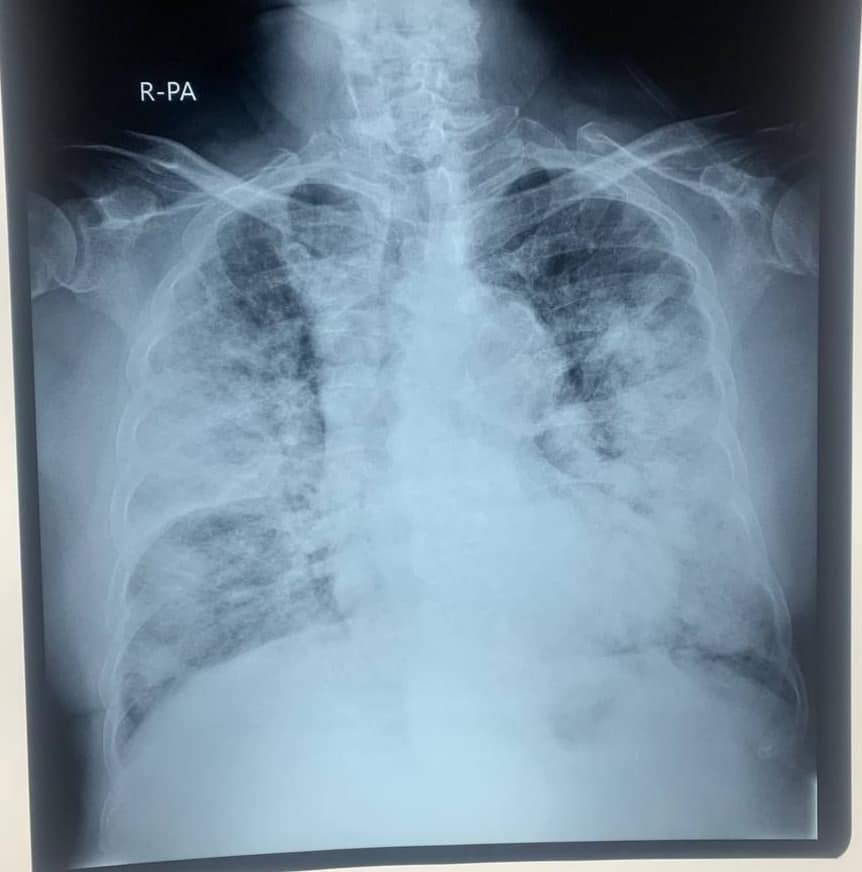

“មានបទពិសោធន៍ជាង1ឆ្នាំក្នុងគ្រប់គ្រង និងព្យាបាលជំងឺកូវីដដោយគ្មានការភ័យខ្លាចឬតក់ស្លុតឡើយ ។ តែក្នុង1ខែចុងក្រោយនេះចាប់ពី 20 កុម្ភៈ 2021 ខ្ញុំមានអារម្មណ៍ភ័យខ្លាច និងព្រួយបារម្ភណាស់ ពីព្រោះវាជាប្រភេទមេរោគប្រែរូបថ្មី (variant virus strain) ដែលក្នុងរយៈពេលតែ2ទៅ5ថ្ងៃវាវាយលុកចូលសួតធ្វើអោយរលាកធ្ងន់ធ្ងរទាំងសងខាង ។ រូបភាពសួតត្រូវបានមេរោគស៊ីសុះសាច់ដ៏គួអោយខ្លាច ។